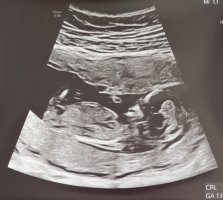

Fikk ta screenshot fra videoen, babyen var så aktiv så var vanskelig å få tydelige bilderVar 12+5 her. Noen som klarer å tyde, gutt eller jente?